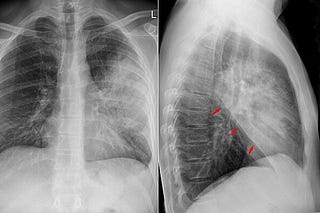

Pneumonia shots also help against viruses, including SARS CoV-2

That's crazy. Quick Boost #12.